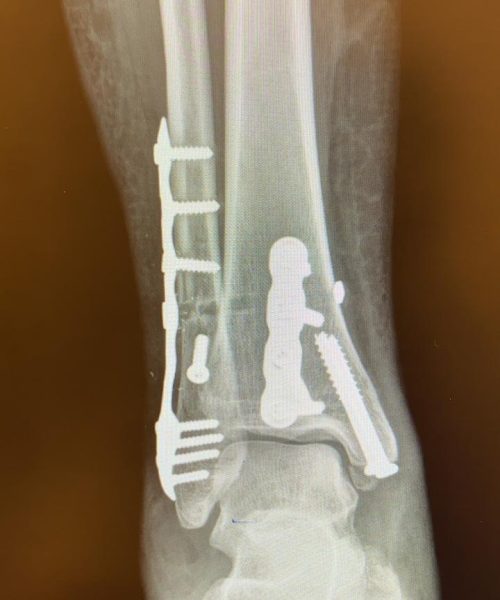

Fraturas no pé e tornozelo referem-se à quebra dos ossos nessas regiões, podendo ocorrer devido a traumas, quedas ou impactos.

Os tratamentos são indicados para pacientes com fraturas que podem variar de simples a complexas, comprometendo a função e a estabilidade.

O tratamento pode incluir imobilização com gesso, tala ou até mesmo cirurgia, dependendo da gravidade da fratura. A cirurgia pode envolver o uso de pinos, placas ou parafusos para fixar os ossos.

Riscos cirúrgicos incluem infecção, má cicatrização óssea e a necessidade de remoção posterior de hardware. O cirurgião deve discutir esses riscos detalhadamente com o paciente.

A recuperação pode variar significativamente, dependendo da gravidade da fratura e do tipo de tratamento. Geralmente, envolve um período de imobilização seguido por fisioterapia para restaurar a função e a mobilidade.